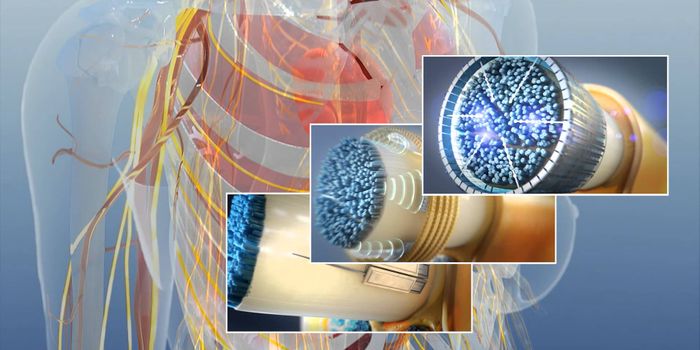

OCT 29, 2018NeuroscienceNerve regeneration by electrical stimulation